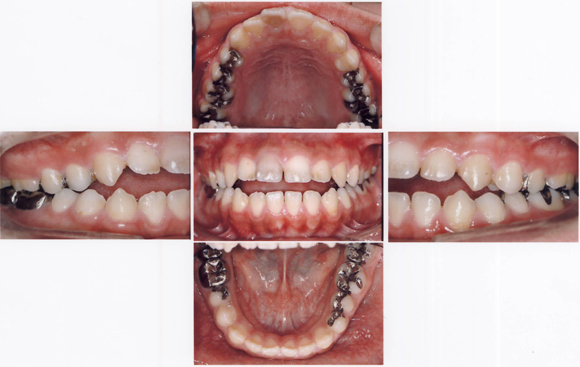

CASE2 開咬(前歯が咬み合わず開いている)ケース

術前

術後